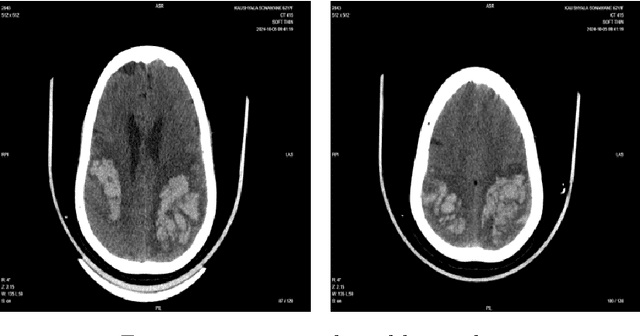

Abstract:Background: Intracranial bleeding (IB) is a life-threatening condition caused by traumatic brain injuries, including epidural, subdural, subarachnoid, and intraparenchymal hemorrhages. Rapid and accurate detection is crucial to prevent severe complications. Traditional imaging can be slow and prone to variability, especially in high-pressure scenarios. Artificial Intelligence (AI) provides a solution by quickly analyzing medical images, identifying subtle hemorrhages, and flagging urgent cases. By enhancing diagnostic speed and accuracy, AI improves workflows and patient care. This article explores AI's role in transforming IB detection in emergency settings. Methods: A U-shaped 3D Convolutional Neural Network (CNN) automates IB detection and classification in volumetric CT scans. Advanced preprocessing, including CLAHE and intensity normalization, enhances image quality. The architecture preserves spatial and contextual details for precise segmentation. A dataset of 2,912 annotated CT scans was used for training and evaluation. Results: The model achieved high performance across major bleed types, with precision, recall, and accuracy exceeding 90 percent in most cases 96 percent precision for epidural hemorrhages and 94 percent accuracy for subarachnoid hemorrhages. Its ability to classify and localize hemorrhages highlights its clinical reliability. Conclusion: This U-shaped 3D CNN offers a scalable solution for automating IB detection, reducing diagnostic delays, and improving emergency care outcomes. Future work will expand dataset diversity, optimize real-time processing, and integrate multimodal data for enhanced clinical applicability.